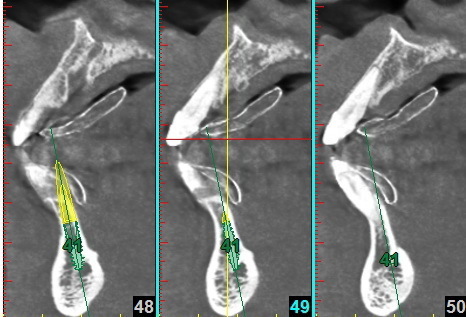

Dans les cas d’extractions-implantations immédiates multiples mandibulaires, il est souvent indiqué de réséquer la crête osseuse avant d’implanter.

La mise en place de 5 implants entre les deux trous mentonniers nécessite souvent un guide chirurgical sur mesure. Dans cette simulation, les implants sont colorisés en vert , les vis de fixation en violet et les deux nerfs dentaires en orange.

Le premier guide (en bas sur la photo) permet de réséquer la crête en vue de la pose des 5 implants à l’aide du second guide (en haut sur la photo). Les ouvertures supplémentaires permettent de fixer le guide avec les deux vis d’ostéosynthèse (violettes dans la simulation).